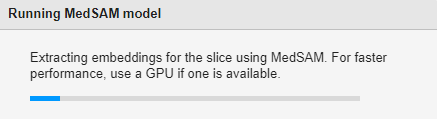

If you are segmenting objects in a medical image or a 2-D slice image of a medical volume for the first time in the app, and if you are not using a GPU, the MedSAM algorithm takes some time to extract embeddings for the image. In this case, the app displays the Running MedSAM model dialog box.